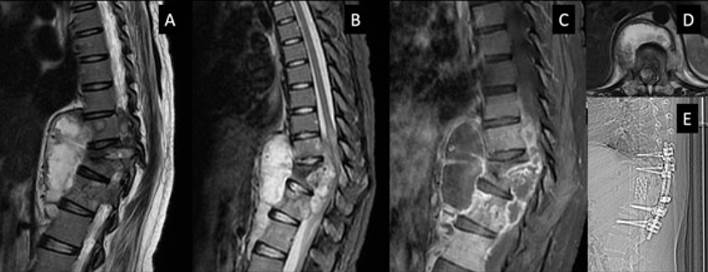

Abordaje posterior: Es el abordaje que se utiliza con más frecuencia, debido a la facilidad, familiaridad del cirujano y la capacidad para lograr la artrodesis circunferencial junto con el desbridamiento anterior. Hoy en día, la tendencia es la reconstrucción anterior/posterior solo por el abordaje posterior, que puede ser transpedicular, transarticular, costotransversectomía y/o extrapleural. Los dos últimos procedimientos son los mejores para lograr una mejor exposición de la columna torácica 14,18,57-59 (Figura 3). El hueso viable solo debe extraerse para descomprimir la médula espinal y el espacio resultante debe cubrirse con un injerto óseo 24.

Figura 3 Varón de 63 años, con afectación vertebral D9 y D10, en etapa IV de destrucción vertebral, déficit neurológico Kumar 3 (con paraparesia 2/5 y compromiso de esfínteres). A: RM sagital en T2 que muestra destrucción y colapso de vértebra D9 y D10, lesiones heterogéneas a predominio paradiscal y lesión intracanal con compresión medular. B: RM sagital en T1. C: Imagen intraoperatoria, luego de la costotransversectomía izquierda D10 y la exéresis de la lámina D9 y D10, así como de la articulación facetaria y exéresis parcial del pedículo D9 izquierdo, se observa saco dural (punto negro), granuloma anterior al saco dural (flecha negra) y parte del pedículo D9 (asterisco blanco). D: Desbridamiento y espacio entre los cuerpos vertebrales (cabeza de flecha negra).